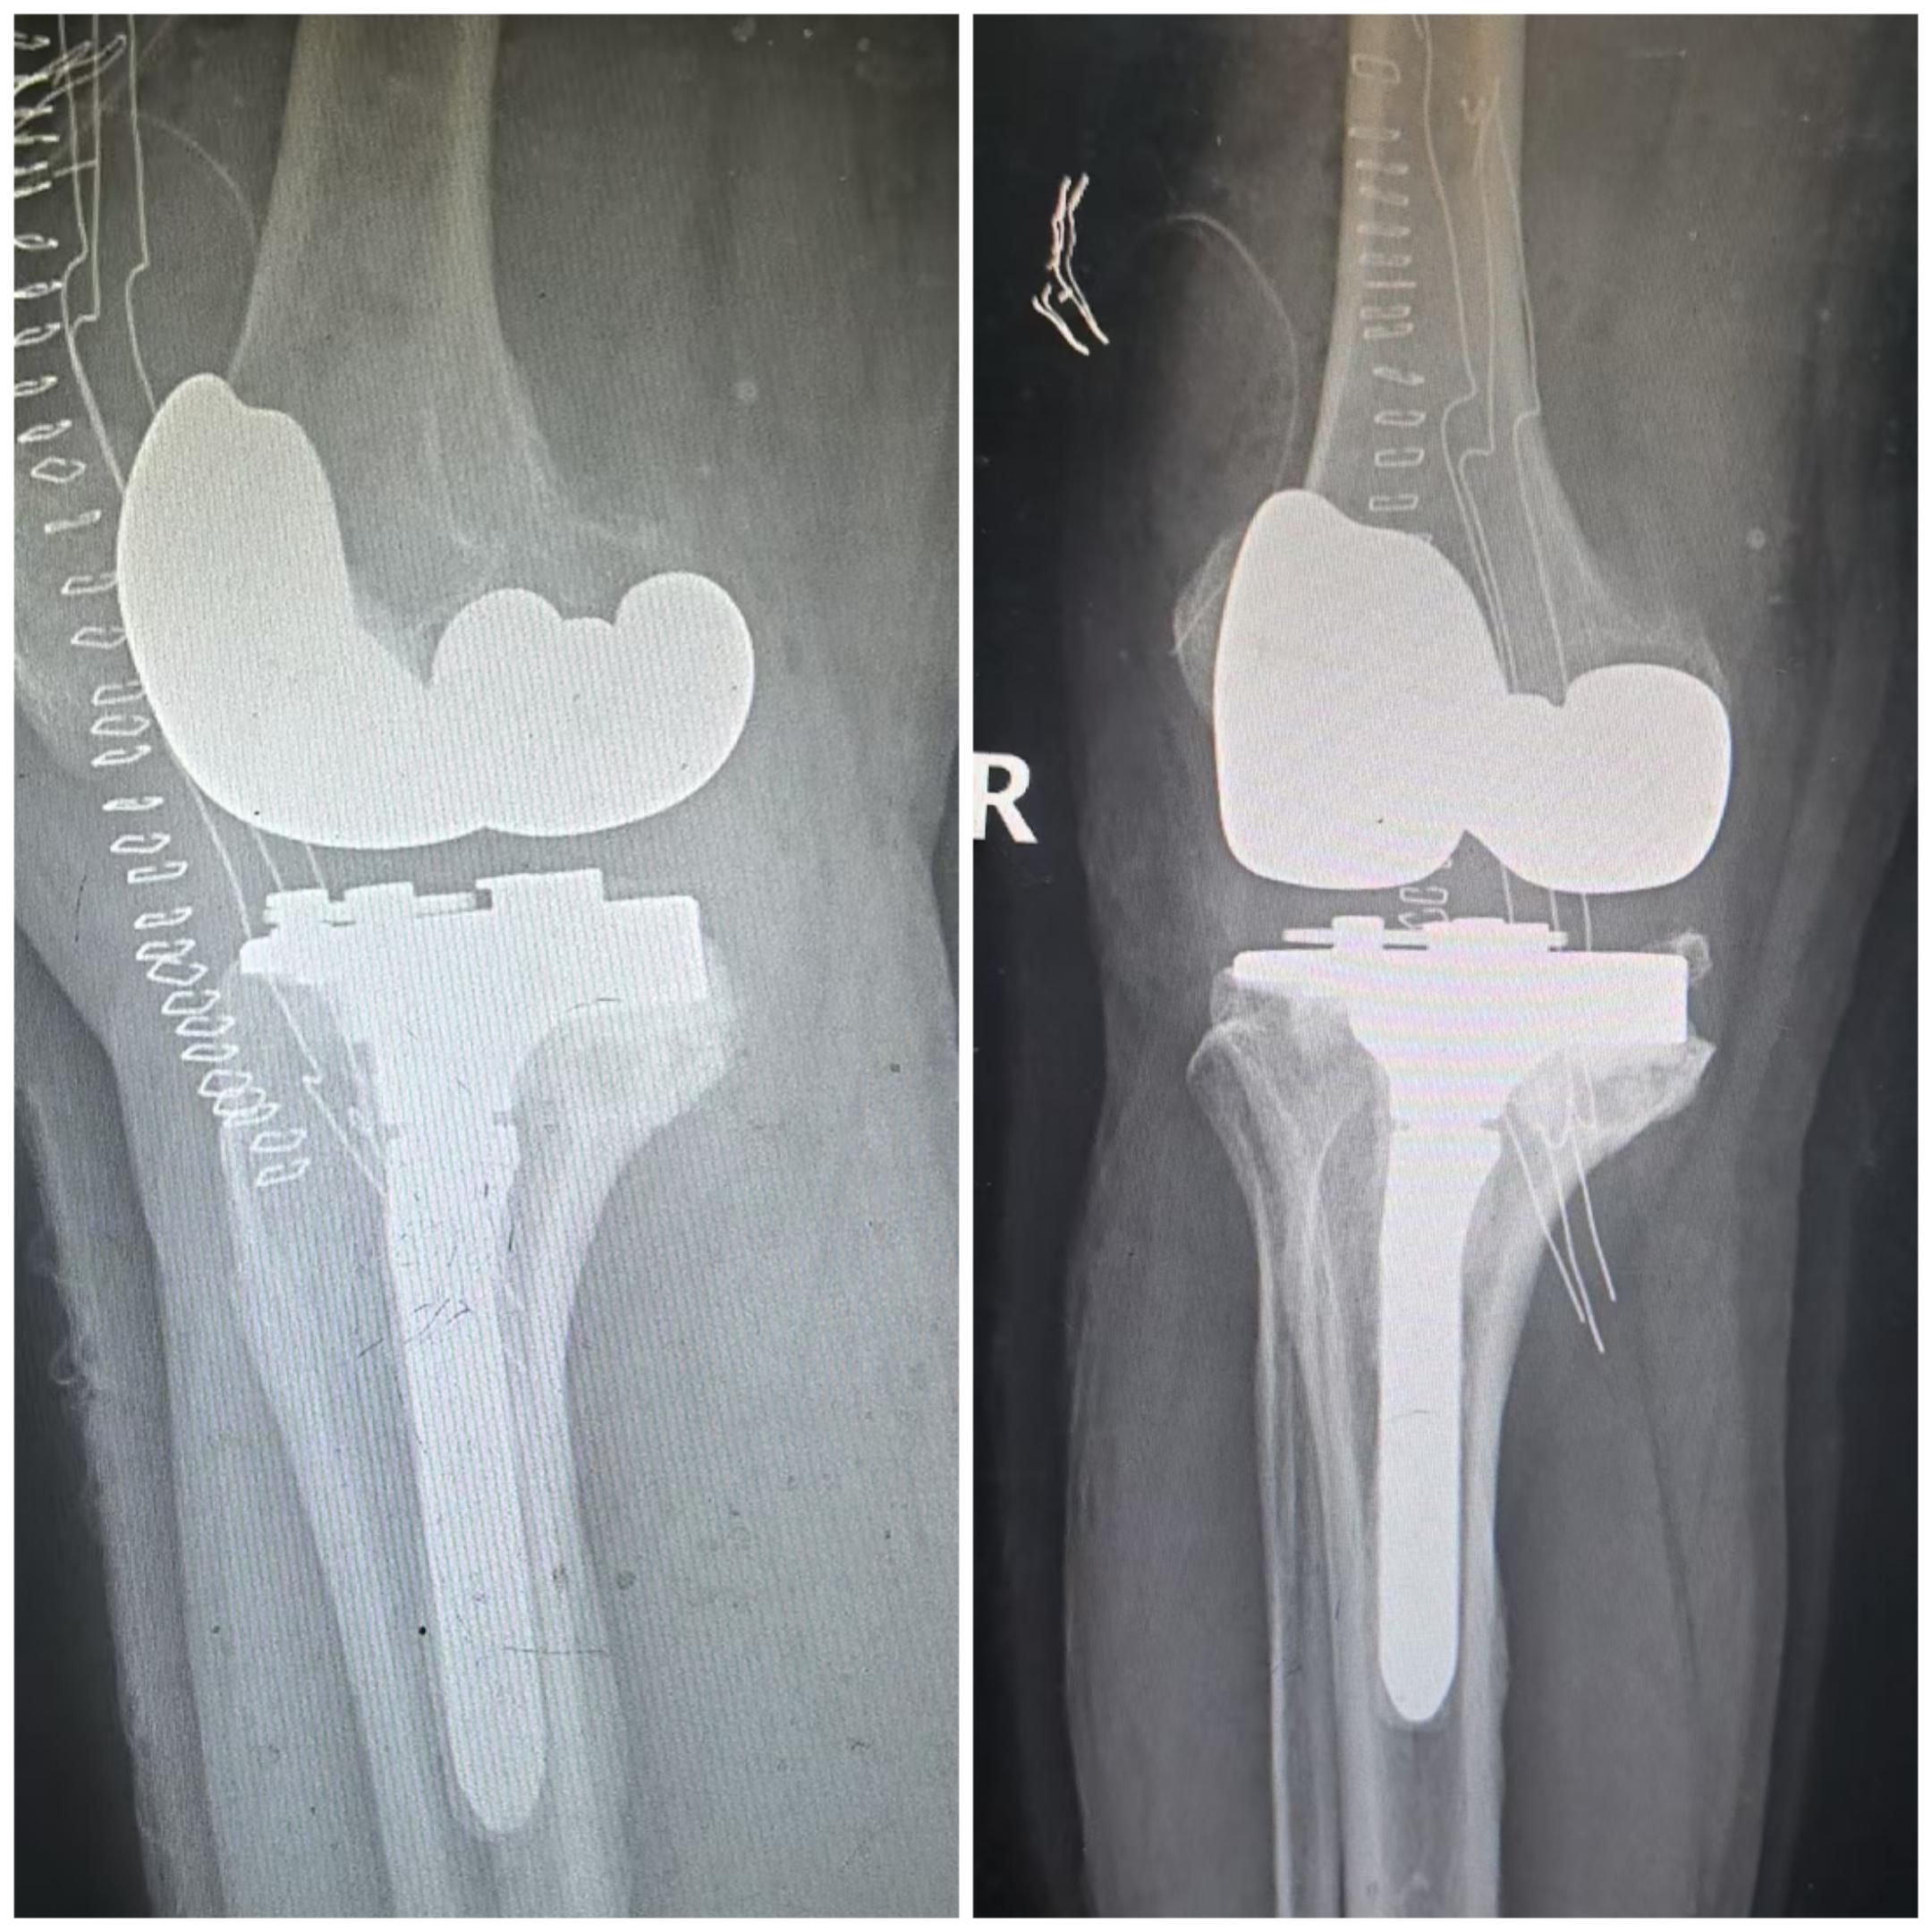

单髁置换术后全膝翻修。单髁置换术后假体松动,双侧全膝翻修。还是那句话,UKA一定严格把握适应症,掌握手术技术要点,才能用的长久。